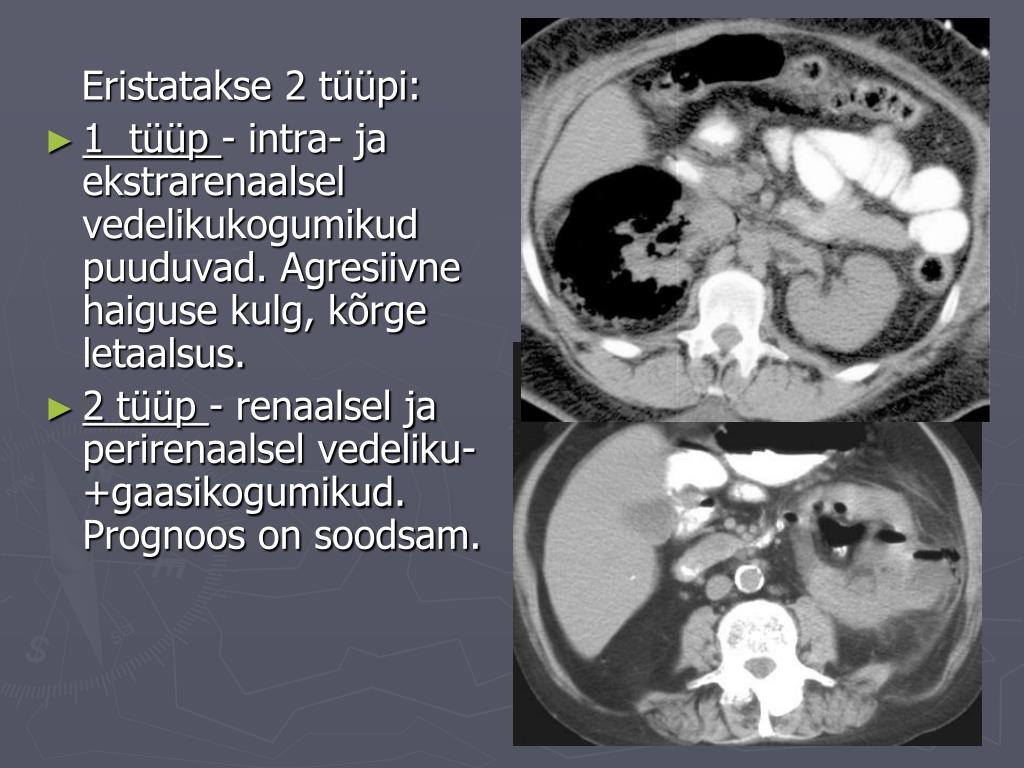

23. KT • neerud suurenenud • gaasikogumikud • vedelikukogumikud • gaasi-vedeliku nivoo • fokaalne neeruparenhüümi nekroos abstsessiga või ilma

24. Eristatakse 2 tüüpi: • 1 tüüp - intra- ja ekstrarenaalsel vedelikukogumikud puuduvad. Agresiivne haiguse kulg, kõrge letaalsus. • 2 tüüp - renaalsel ja perirenaalsel vedeliku- +gaasikogumikud. Prognoos on soodsam.